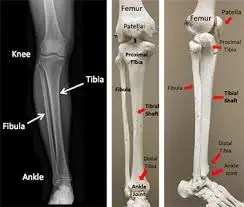

tibia shin bone location anatomy common conditions 394×351

tibia shin bone location anatomy common conditions

tibia shin bone medial bone  fibula lateral bone diagram quizlet 572×442

tibia shin bone medial bone fibula lateral bone diagram quizlet